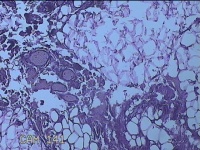

外阴部包块

性别

女

年龄

37岁

临床诊断

皮脂腺囊肿

一般病史

外阴部起包块一月余。

标本名称

大体所见

灰白暗红色包块2.3x1.8x0.8cm一个,表面糜烂,切开包块呈实性,切面灰白淡黄色,质软。

有那么点像脂肪瘤。